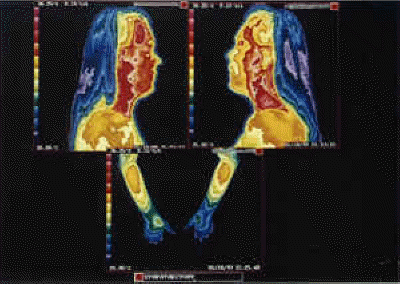

Virtual Sympathectomy Thermography.

"Virtual sympathectomy" secondary to repeated stellate ganglion nerve blocks leading to permanent sympathetic nerve damage and hyperthermia (heat leakage) in upper extremities. The ITI spared the patient from further sympathetic nerve blocks.

Thermography of the face and hands after Sympathectomy.

Thermography of the Hands (After Virtual Sympathectomy). More than two dozen stellate ganglion blocks to each side have damaged enough sympathetic nerve to cause permanent hyperthermia as the manifestation of virtual sympathectomy. Further blocks have no diagnostic or therapeutic value.